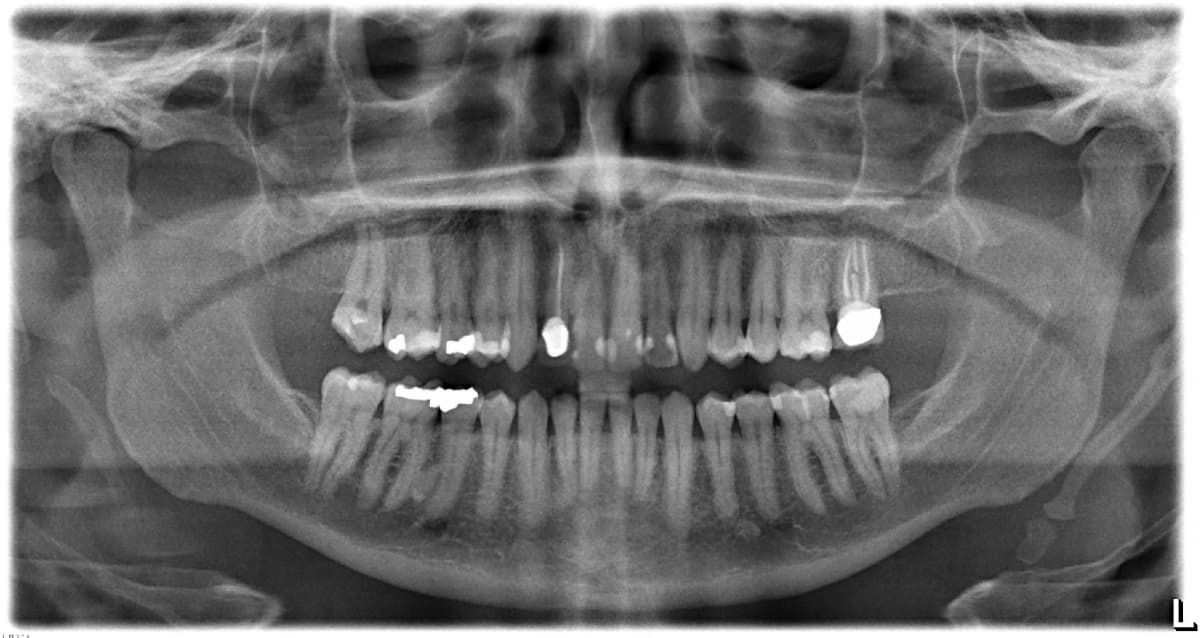

Provide a wide view of the entire mouth, including all teeth, jaws, sinuses, and surrounding structures in a single image, ideal for assessing wisdom teeth and jaw problems.